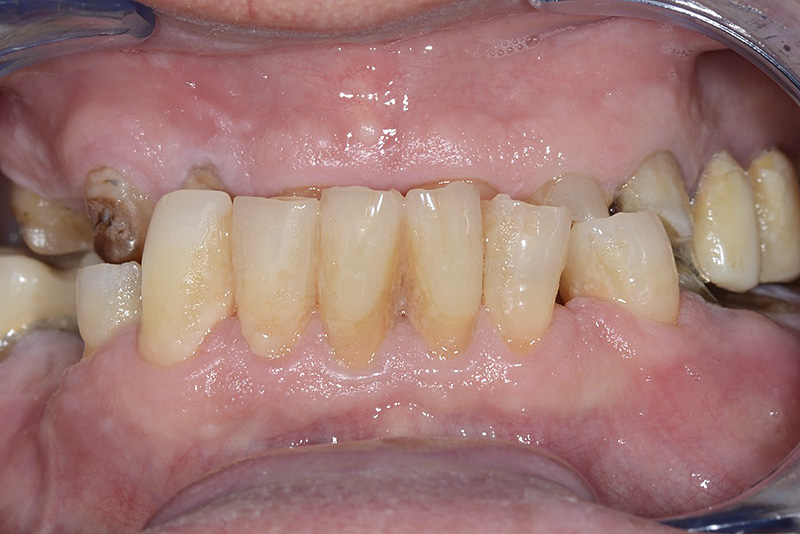

PREMESSA: in seguito all’estrazione dell’incisivo laterale superiore di destra, resasi necessaria per cause batteriche, si decide di affrontare il caso con il posizionamento di un impianto in sostituzione dell’elemento mancante dopo guarigione del sito infetto. Con tecniche rigenerative sia dei tessuti ossei mancanti a causa dell’infezione pregressa, sia dei tessuti gengivali che appaiono inizialmente troppo spostati in alto, si ripristina una corretta morfologia delle parabole (contorni) gengivali e delle papille interdentali (triangoli di gengiva tra due denti vicini).

Vengono utilizzati 2 tipi di provvisori: il primo, cementato ai denti vicini, viene utilizzato dal momento dell’estrazione del dente fino ad impianto osteointegrato (circa 6 mesi); il secondo, avvitato direttamente all’impianto, ha una funzione di prova estetica ma soprattutto di guida per la maturazione dei tessuti gengivali peri-implantari portandoli verso la maturazione completa prima di posizionare la corona finale in disilicato di litio.